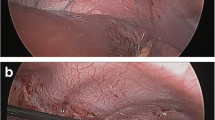

Mapping involves finding the motor point of the diaphragm where stimulation causes the greatest contraction of the diaphragm. The mapping instrument is held onto the diaphragm by suction with stimulation from a clinical station, and both qualitative and quantitative data is obtained from the stimulation (Fig. 1). Quantitatively, changes in abdominal pressures are measured from one of the laparoscopic ports. Qualitatively, visual observation of the diaphragm motion during a stimulated contraction is used to assess the optimal location for lead implantation. The stronger the stimulated contraction, the closer the mapping probe is to the motor point of the diaphragm. Two electrodes are implanted: one at a primary site and one at a secondary site to capture additional diaphragm movement. Electrodes are then implanted using the electrode implant instrument (Fig. 2). The needle at the end of the instrument is placed into the diaphragm muscle and on withdrawal the barb on the end of the electrode releases, allowing the exposed electrode to stay in the muscle. These electrodes along with an anode are tunneled to an appropriate spot on the chest or abdominal wall. If the patient has a cardiac pacemaker, it is simultaneously interrogated while the diaphragm is being paced, to confirm no device-to-device interactions. Testing is performed at nominal and most sensitive sensing settings for the cardiac pacemaker and in sensing modes supported by the cardiac pacemaker, e.g., unipolar and bipolar sensing. Chest X-ray is obtained to evaluate for the presence of a large capnothorax from the insufflated carbon dioxide that may have tracked from the abdominal cavity through the diaphragm. A small capnothorax resolves spontaneously while a larger one may need to be aspirated.

A significant difference was noted in the ALS diaphragms. Figure 3 shows the appearance of the partially denervated diaphragm, showing radial bands of pale denervated muscle. The ALS diaphragms had weaker contractions with the typical mapping stimulation. At times no quantitative change in abdominal pressure was sensed and no qualitative observation of diaphragm movement was seen. In these cases burst stimulation was then used, which involved using a train of stimulation of 1 s (Fig. 4). This would cause diaphragm movement and confirm the optimum motor point for implantation. If the diaphragm was significantly weaker the abdominal insufflation pressure would be lowered to allow visualization of diaphragm movement. Using these additional techniques allowed appropriate implantation of DPS electrodes in all of the ALS patients. Postoperative management was also different between the two groups of patients. SCI patients were easily returned to their ventilators postoperatively with no respiratory events. The ALS patients had significant respiratory compromise preoperatively yet were not on ventilators preoperatively. One of the safety aspects that was tracked during the trial was the ability to safely extubate these patients postoperatively. All patients who were on noninvasive positive-pressure ventilation (NIPPV) preoperatively were immediately placed back on NIPPV in the recovery room. Also short-acting narcotics and amnestics were used during the procedure to decrease the chance for respiratory drive suppression at the case conclusion. It was identified early in the study that ALS patients were being extubated more easily than expected. This was studied in ten of the subjects by measuring the respiratory system compliance at the end of the procedure. DPS was synchronized with the anesthesiology ventilator and the change of respiratory compliance was measured before and after the use of DPS [15]. There was a 19% increase of respiratory compliance when DPS was used. DPS was done routinely at the end of the procedure to help with extubation.

Twitch versus burst stimulation patterns. Mapping diaphragms involves a single twitch stimulation with quantitative measurement of abdominal pressures and qualitative assessment of diaphragm contraction. In a partially denervated diaphragm a twitch will not give a consistent abdominal pressure so a burst of 1 s (usually used when actually breathing for a patient) will allow a qualitative assessment of diaphragm contraction